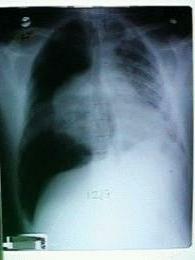

While you are waiting for the x-ray

technician to develop the x-ray, your patient's blood pressure continues to fall and

she has an asystolic cardiac arrest. In the middle of the resuscitation, the

x-ray technician shows you an interesting CXR. Click on the image at left to see an enlargement.